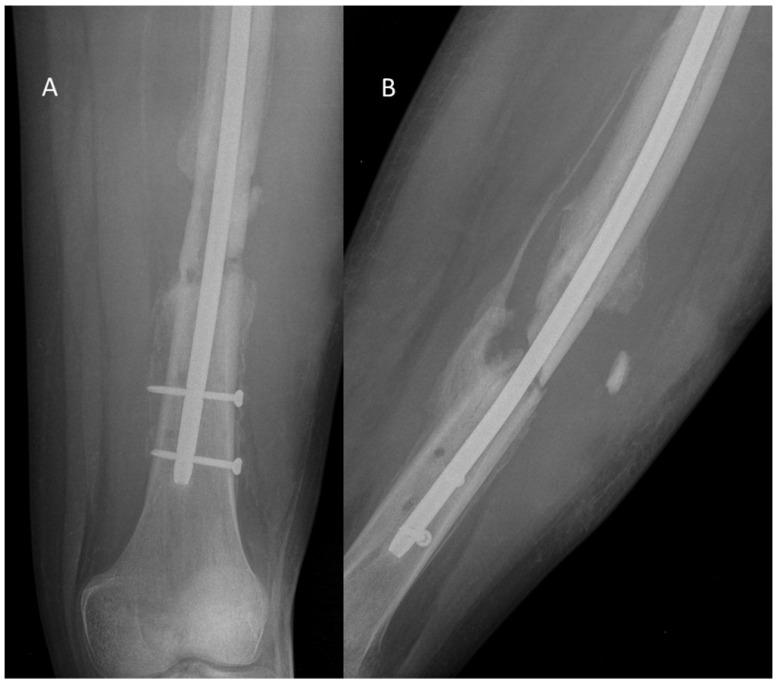

Osteomyelitis, a severe bone infection, poses a significant therapeutic challenge in both human and veterinary medicine, especially due to the increasing prevalence of antibiotic-resistant pathogens like methicillin-resistant Staphylococcus aureus (MRSA). Conventional treatments, including surgical debridement and systemic antibiotics, often prove inadequate due to the ability of bacteria to form biofilms and evade host immune responses. Antimicrobial peptides (AMPs), such as LL-37 and β-defensins, have emerged as a promising alternative therapeutic strategy. AMPs exhibit broad-spectrum antimicrobial activity, including efficacy against resistant strains, and possess immunomodulatory properties that can promote bone regeneration. This article comprehensively reviews AMP applications in treating osteomyelitis across both human and veterinary medicine. We discuss diverse therapeutic approaches, including free AMPs, their conjugation with biomaterials such as collagen and chitosan to enhance delivery and stability, and the development of AMP-based nanoparticles. Furthermore, we analyze preclinical and clinical findings, highlighting the efficacy and safety of AMPs in combating osteomyelitis in both human and animal patients. Finally, we explore future perspectives and challenges, such as optimizing delivery, stability, and efficacy, while minimizing cytotoxicity, and in translating AMP-based therapies into clinical practice to effectively manage this debilitating disease.